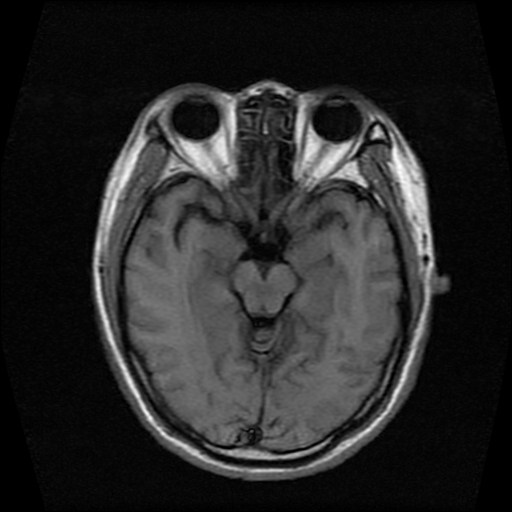

标题: MRI2584:静脉窦血栓?请会诊!

男性,39岁。头晕,视物模糊2月余。血压142/85。矢状窦内高信号有问题吗?

正常脂肪信号影。

正常,若不放心,可以mrv证实

这种病例以前也见过, 但平常的阅片过程比较少注意,而且一些资料上介绍或者图片也比较少,我觉得此病例应该考虑静脉窦血栓。

起码近来我注意的正常人静脉窦内部不是如此信号。

t1wi像可以出现缓慢流速血管呈高信号,应加t2wi及mrv